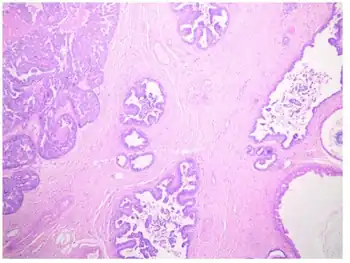

Papillomatosis of skin is skin surface elevation caused by hyperplasia and enlargement of contiguous dermal papillae.[1] These papillary projections of the epidermis form an undulating surface under microscopic examination.